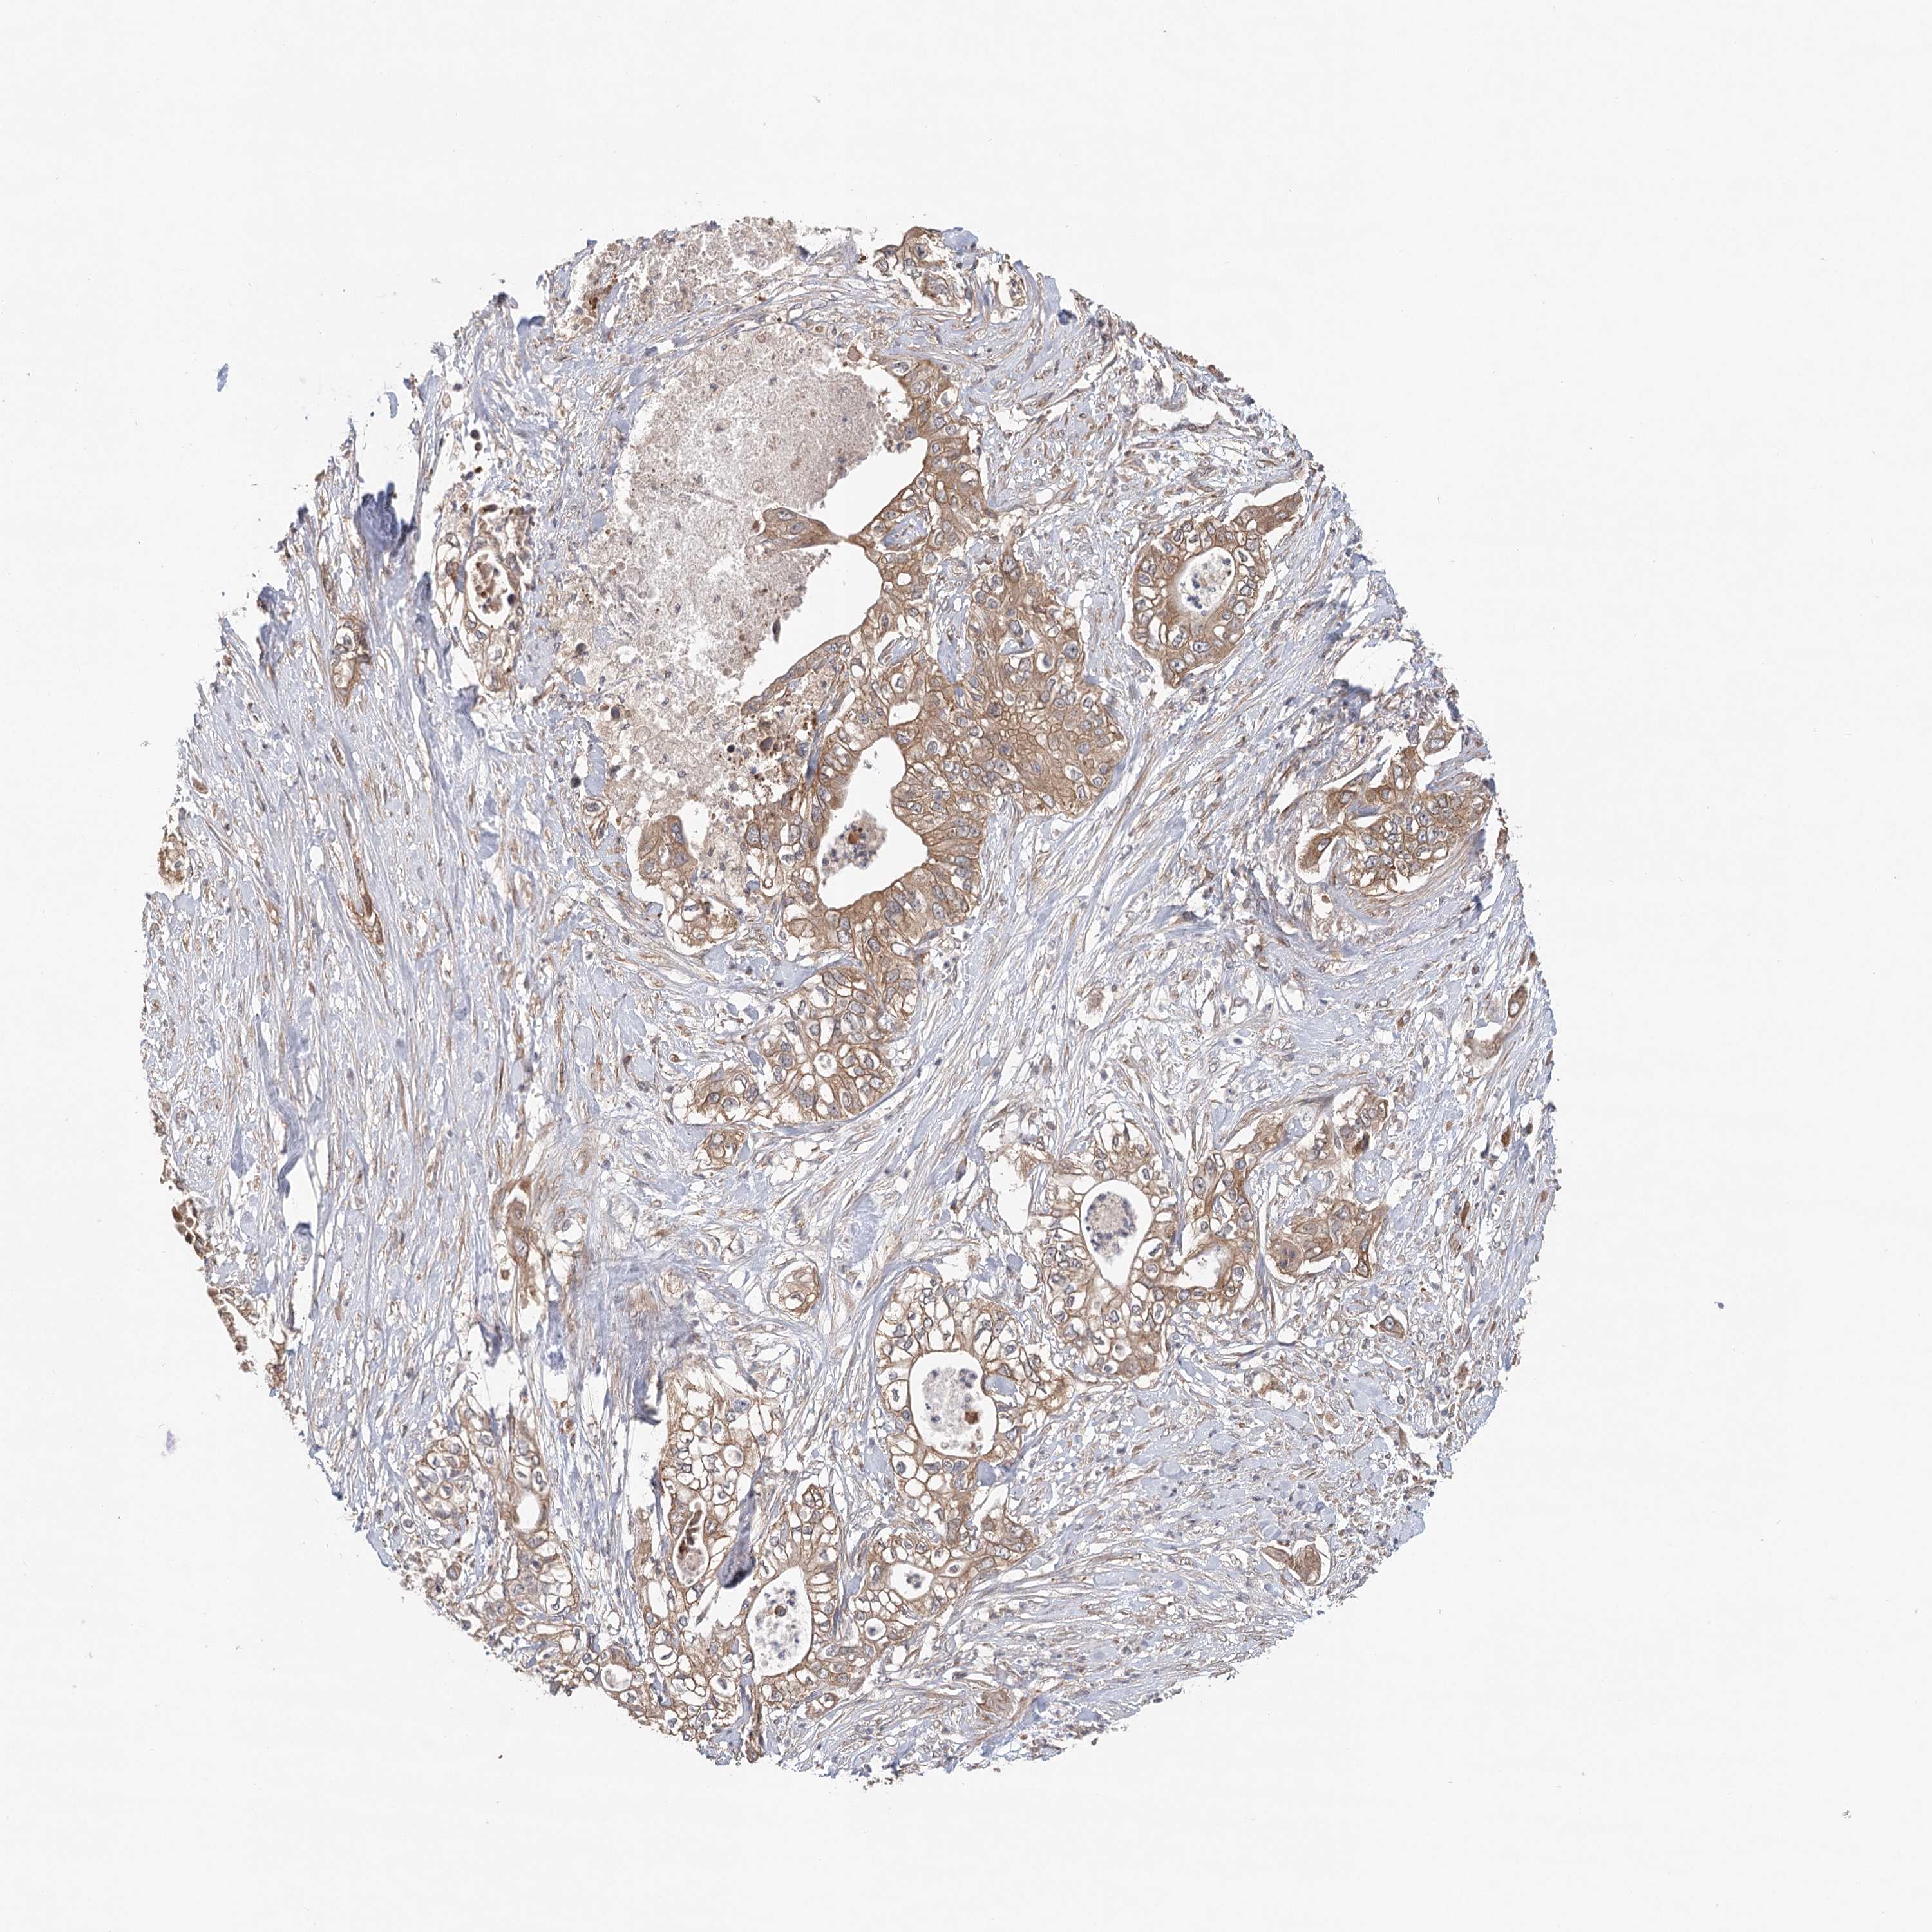

PANCREATIC CANCER - Protein expressioni

A mouse-over function shows sample information and annotation data. Click on an image to view it in a full screen mode. Samples can be filtered based on level of antibody staining by selecting one or several of the following categories: high, medium, low and not detected. The assay and annotation is described here.

Note that samples used for immunohistochemistry by the Human Protein Atlas do not correspond to samples in the TCGA dataset.

Antibody stainingi

Antibody staining in the annotated cell types in the current human tissue is reported as not detected, low, medium, or high, based on conventional immunohistochemistry profiling in selected tissues. This score is based on the combination of the staining intensity and fraction of stained cells.

Each image is clickable and will lead to virtual microscopy that enables deeper exploration of all samples and also displays staining intensity scores, fraction scores and subcellular localization as well as patient and tissue information for each sample.

Antibody HPA032060

Antibody HPA032062

Antibody CAB034116

Staining

High

Medium

Low

Not detected

Intensity

Strong

Moderate

Weak

Negative

Quantity

>75%

75%-25%

<25%

None

Location

Nuclear

Cytoplasmic/membranous

Cytoplasmic/membranous,nuclear

Adenocarcinoma, NOS